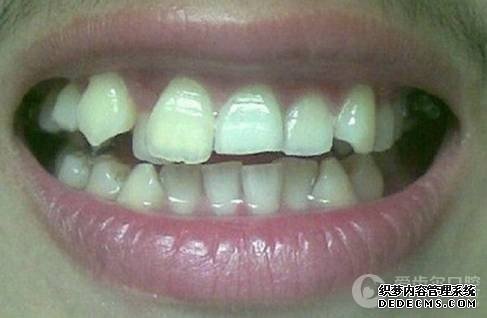

基本信息:项先生,29岁,IT,经朋友介绍就诊

患者自述:眼看快到而立之年,身边好友都已成家立业,可我依然孤身一人,难免有些落寞。可是因为牙齿不齐,让我总是缺乏自信,性格也变得内向腼腆,几次相亲都被心仪的女孩拒绝。为了不被自卑心吞噬,我决定通过牙齿正畸改变自己,给自己一次幸福的机会。

临床诊断:通过3D数字化全景机的拍片检查,患者上下牙排列拥挤,前牙受挤压向内歪斜,咬合关系异常,唇形尚可,颞下颌关节检查未见异常,无蛀牙、牙周疾病症状。经过和患者商量,选定自锁托槽矫正方案,调整牙间隙,恢复牙齿的正常排列,实现正常的咬合关系。

矫正前旧照

矫正前照片